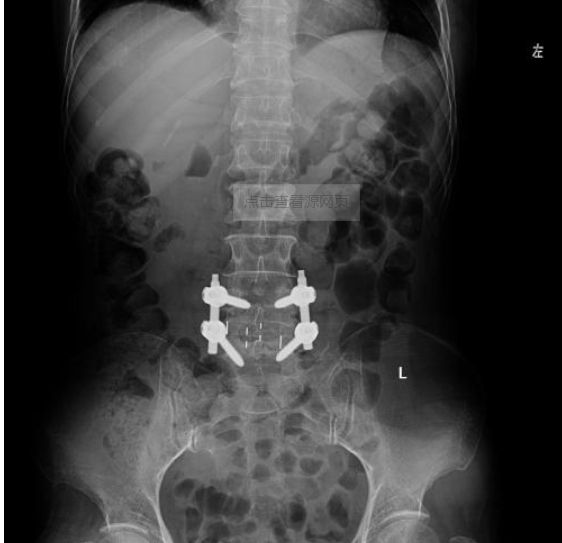

①开放手术(PLIF、TLIF、OLIF、ALIF)

图片 14341

图片 14349 图片 14350